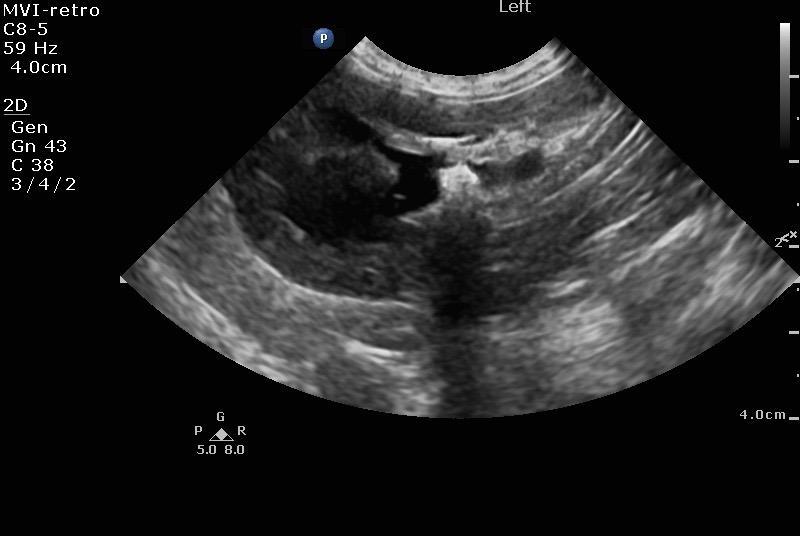

Mild pyelectasia was noted in the left kidney at 4.62 cm and pyelectasia is at 1.01 cm. The left kidney presented a slight amount of perinephric free fluid suggestive for inflammation. Right kidney presented moderate pyelectasia 1.35 cm with obstructed proximal ureter calculus 0.5 cm. Right kidney measured 5.36 cm.

The urinary bladder and trigone presented normal wall thicknesses with anechoic urine and normal tone. Pelvic urethra was imaged 3 cm beyond the cystourethral junction. No uroliths or sediment were visualized. No evidence of inflammatory or neoplastic changes were noted. Left ureter in this patient presented 0.7 cm calculus and a separate 0.25 cm calculus obstructive the left ureter midway between the kidney and the bladder.